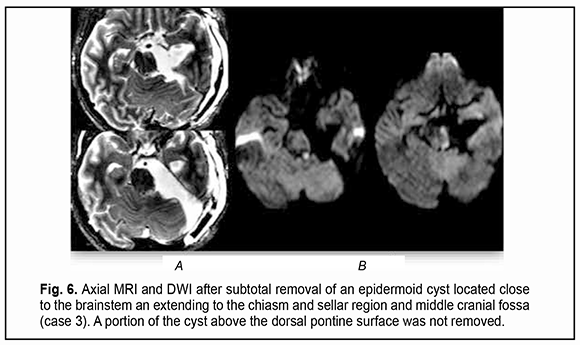

Of the 21 patients, 7 (33.33%) had a gross total removal and 2 (9.53%) had a near total removal of the cyst, with residual capsule fragments not exceeding 2-3 mm (Figs. 4, 5, 6, and 7). In addition, 12 (57.14%) had a subtotal removal of the cyst, with either intraoperative evidence of residual capsule fragments measuring from 2 mm to 10 mm, or postoperative MRI evidence of residual capsule fragments not exceeding 11 mm in the largest dimension. The capsule adhesion to surrounding neurocascular structure at the location where the dissection was difficult was seen in 18 patients (85.7%). In some cases, this can lead to the impossibility of safe total capsule dissection from the brainstem and cranial nerves. Postoperative follow-up ranged from 1 to 12 years, with mean and median values of 38.5 ± 4.8 months and 24 months, respectively (Fig. 8).